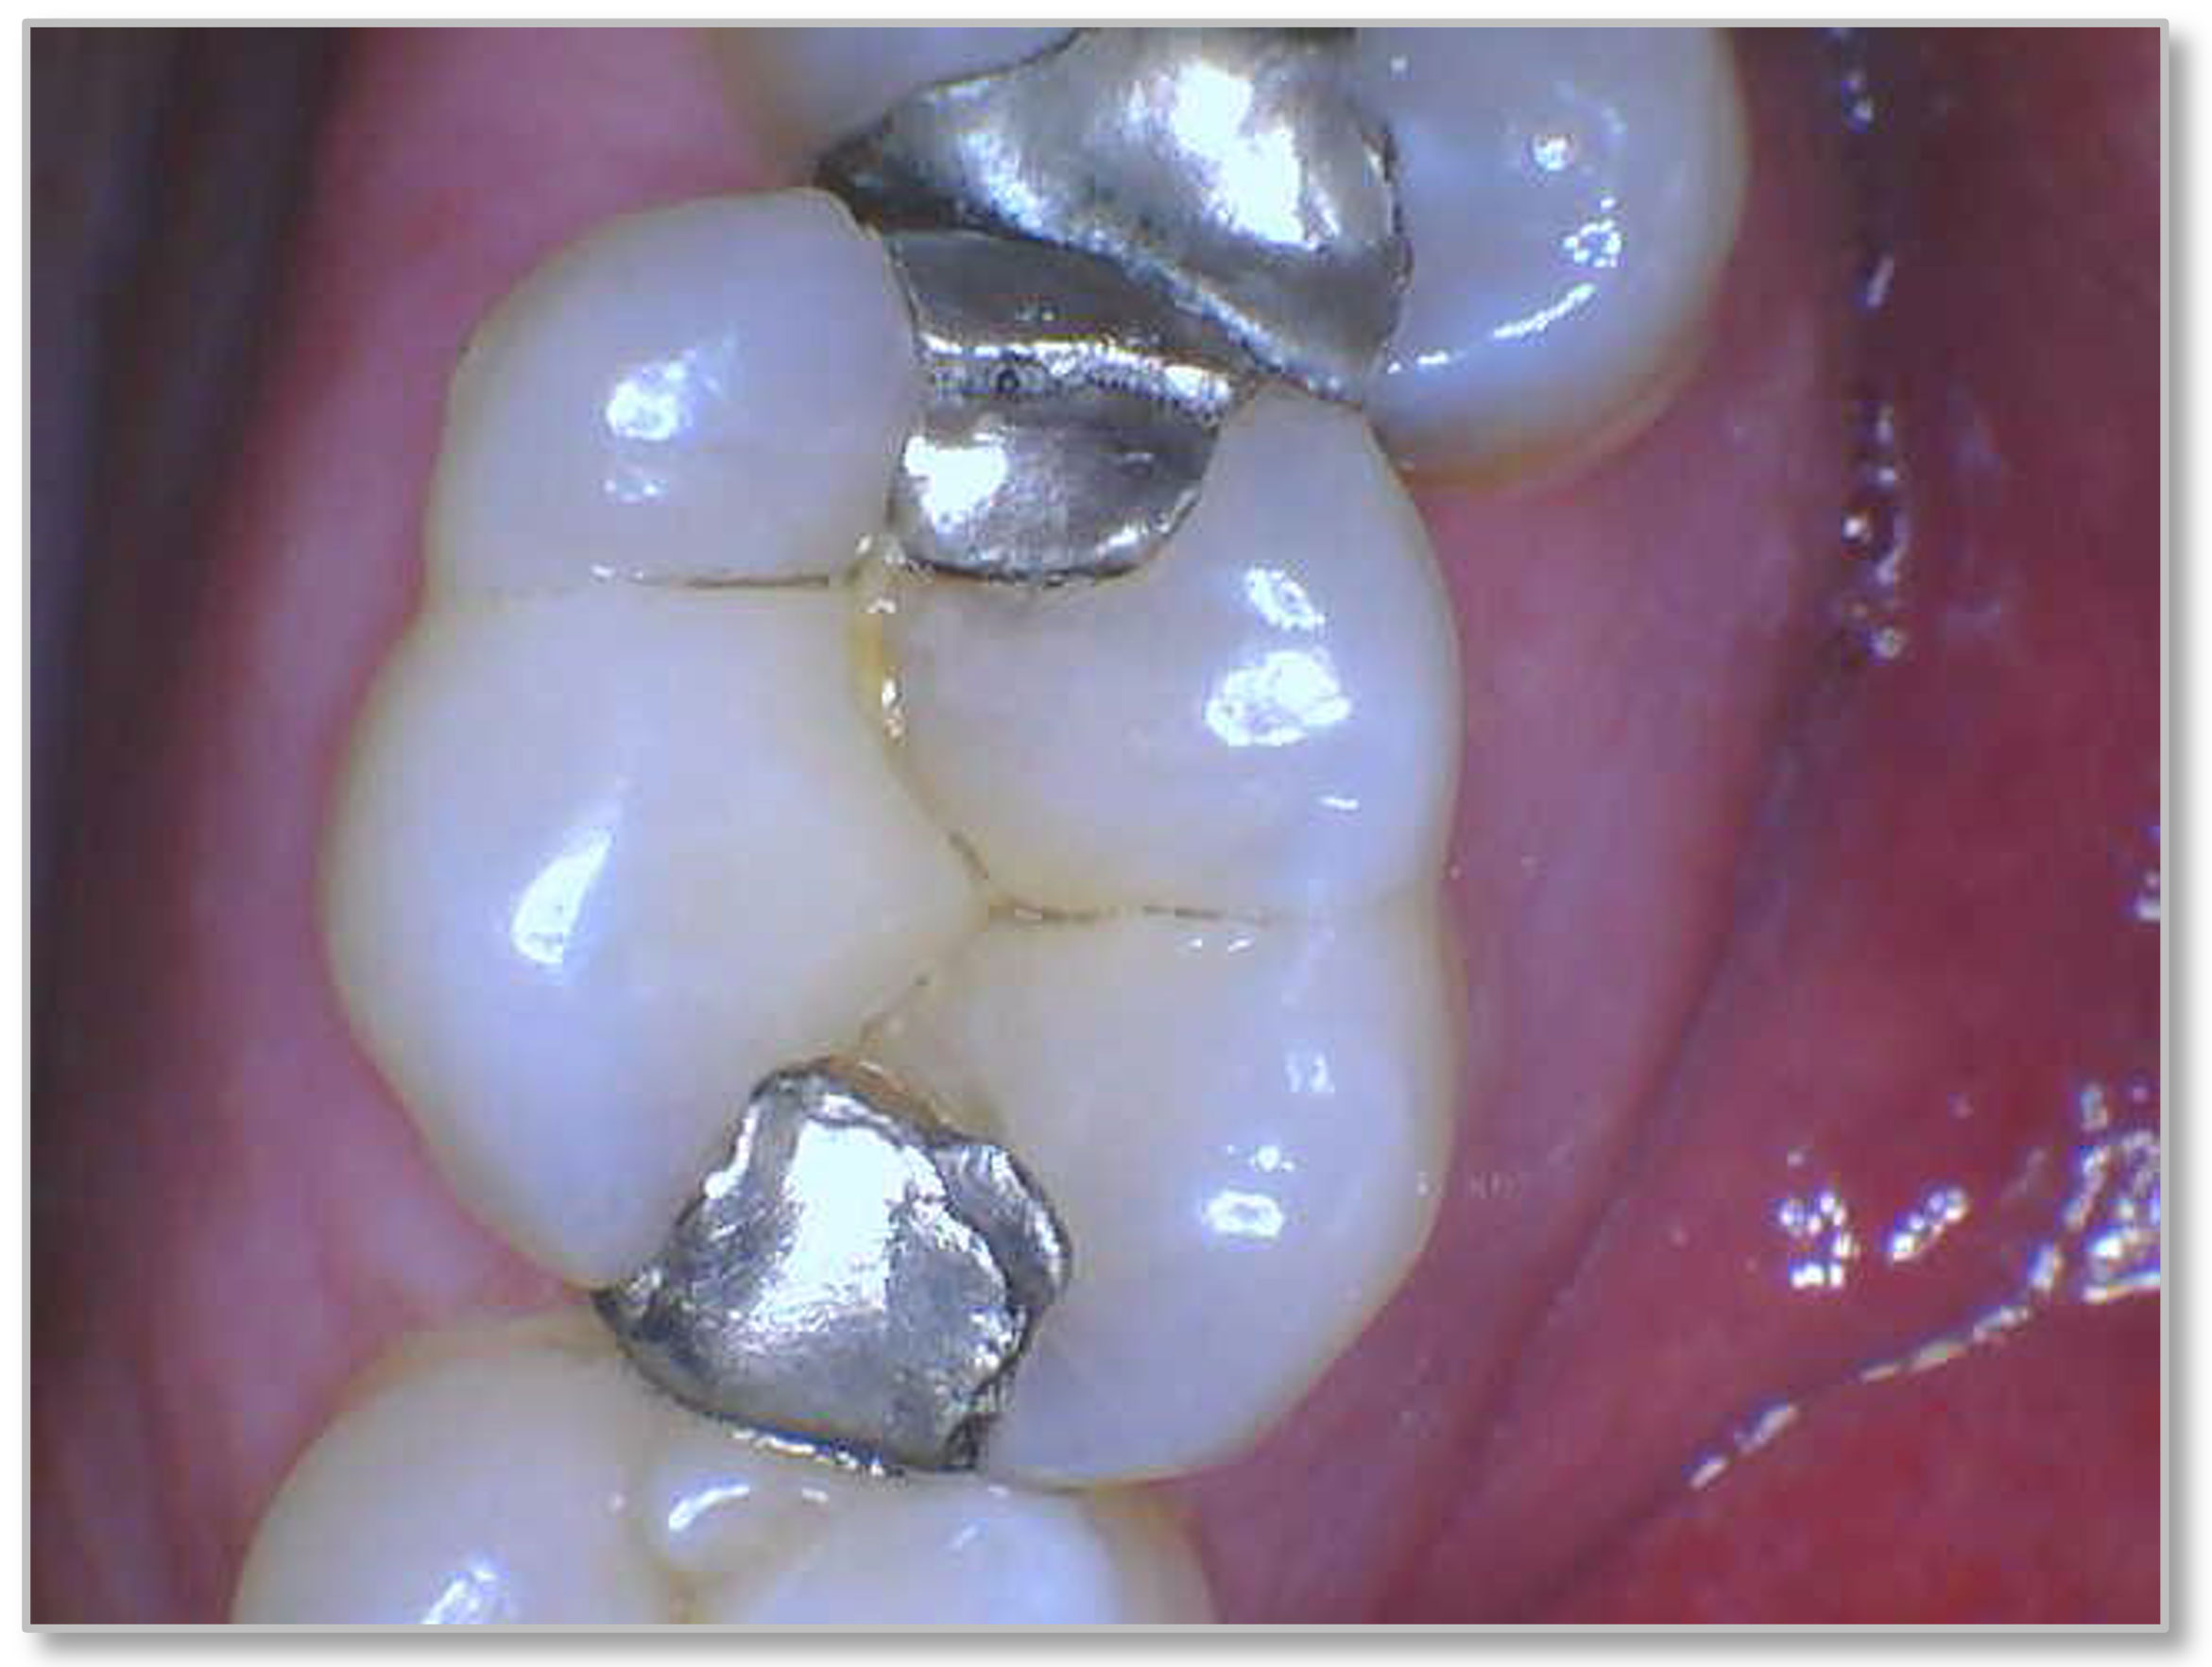

Figure 3a and Figure 3b show a failing composite with stress fractures and interproximal decay. The patient was not in a situation to do an indirect restoration, so the practitioner did a direct composite with good strength and wear characteristics until an indirect restoration could be performed. The composite used in this case is the Kerr SimpliShade Bulk Fill Packable, which in the author's experience also offers good blendability and polishability with good adaptation. Some of the discoloration interproximally is from the bleeding after the rubber dam was removed-which quickly self-resolved.

Fig 3a. A direct composite using Kerr SimpliShade Bulk Fill Packable.

Fig 3a.

Fig 3b. A direct composite using Kerr SimpliShade Bulk Fill Packable.

Fig 3b.